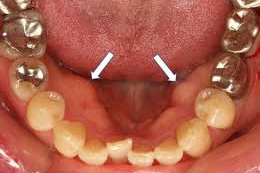

頬粘膜の咬合線(咬合縫線・頬粘膜圧痕)

頬の内側にできる白い線のことで、上下の歯が接触するラインに沿ってできる歯の噛み跡が見られるようになります。

舌の圧痕

舌の側面に歯の形がギザギザと付いて、舌に凹凸が見られるようになります。

骨隆起

歯茎の下などに、コブのように盛り上がった良性の骨の増殖がみられます。